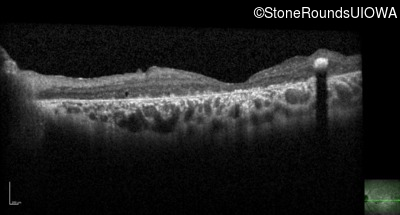

Optical Coherence Tomography - Right - Count Fingers 3'

Exemplar / OCT Stack

OCT Stack